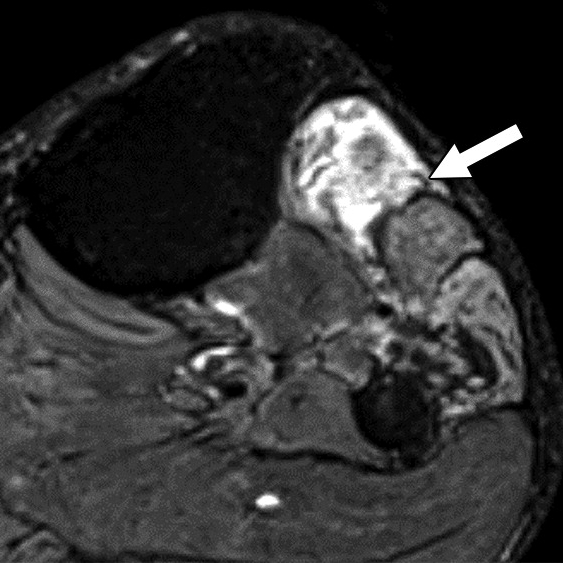

Our retrospective study included 100 patients with nerve imaging examinations and a variety of known clinical diagnoses. Utilizing mutually agreed-upon qualitative benchmarks for classifying and grading peripheral neuropathies, different classes were established to account for the spectrum of underlying pathologies (unremarkable, injury, neoplasia, entrapment, diffuse neuropathy, not otherwise specified, and postintervention state) with subclasses to describe lesion severity or extent. Validation was performed by 11 fellowship-trained musculoskeletal radiologists across 10 institutions, and after initial multimedia training, all 100 cases were blind-presented to readers (Fig. 1).

Offering a uniform lexicon and practical guideline for reporting neuropathic conditions on MRI, ultimately, NS-RADS accuracy for determining milder versus more severe categories per radiologist ranged from 88% to 97% for nerve lesions and from 86% to 94% for muscle abnormalities (Fig. 2).